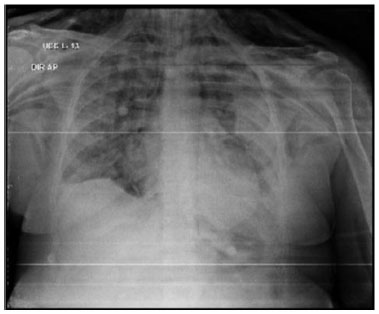

Após o início de VM invasiva, apresentou assincronias frequentes, dificuldade de manter parâmetros VM protetora, com necessidade de ajustes frequentes no ventilador e de associar sedativos em altas doses e bloqueador neuromuscular (fez uso de midazolam, propofol, fentanil e pancurônio). Exame de imagem após intubação orotraqueal, mostrava cânula endotraqueal bem-posicionada, opacidades parenquimatosas difusas, cateter venoso central à direita e sem sinais de pneumotórax (vide figura A). Entretanto, no dia 05/04/21 paciente apresentou ao exame físico enfisema subcutâneo extenso em região torácica e cervical, realizou exames de imagem que evidenciaram extenso enfisema subcutâneo e moderado pneumomediastino (vide figuras B e C). Discutido caso com equipe de cirurgia torácica que optou por manter tratamento conservador e não realizar procedimentos invasivos, como drenagem de subcutâneo.